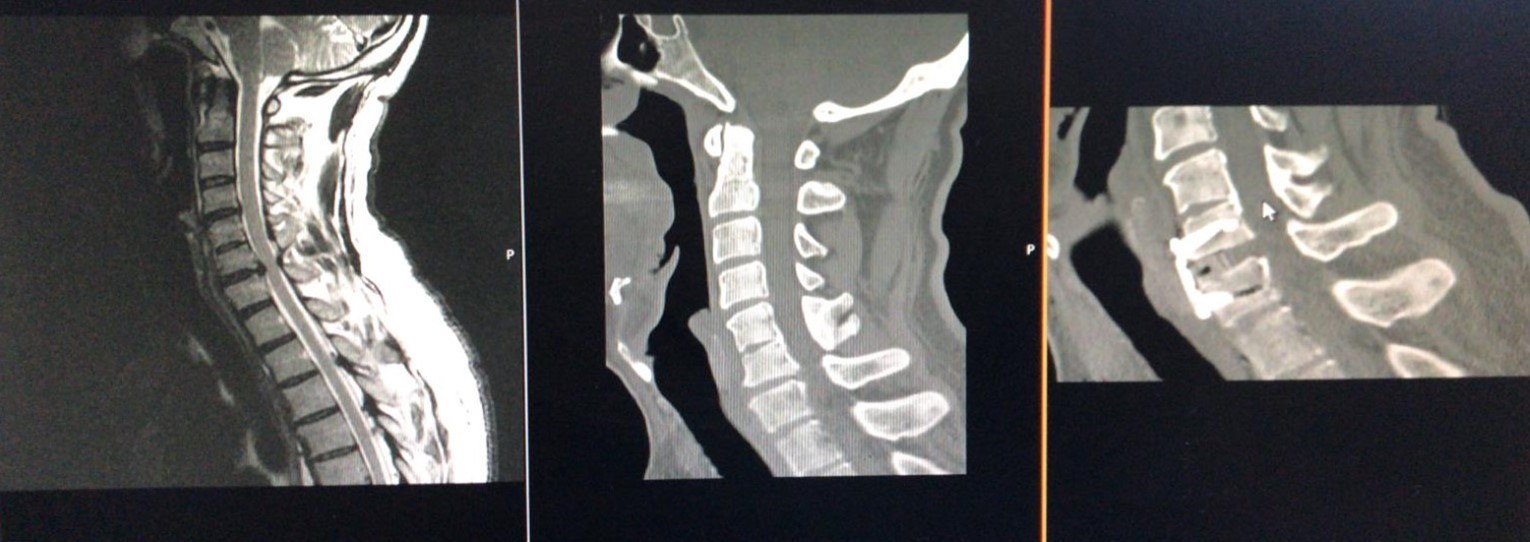

Figure 2.Computerized tomography, and magnetic resonance imaging views of a Yilmaz-Yucesoy Classification System Grade 3 patient who underwent anterior cervical discectomy and fusion with cervical cage and plate.

Computerized tomography, and magnetic resonance imaging views of a Yilmaz-Yucesoy Classification System Grade 3 patient who underwent anterior cervical discectomy and fusion with cervical cage and plate.